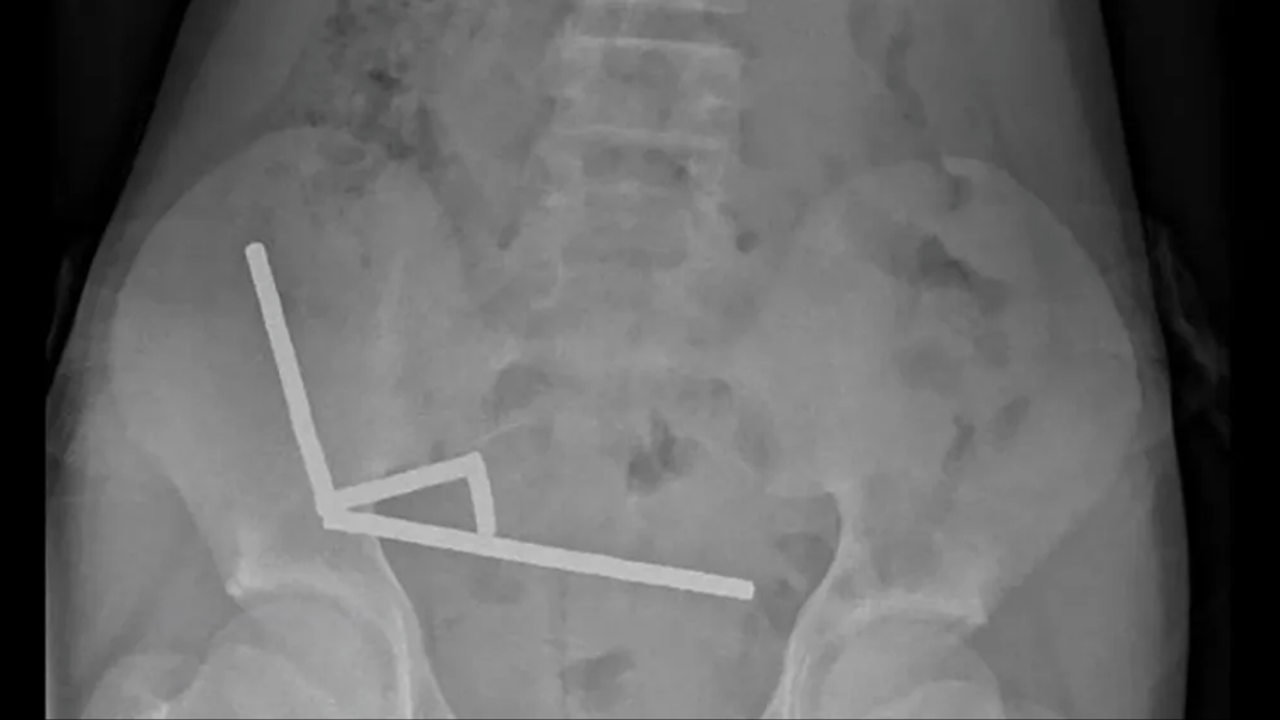

Röntgen görüntülerinde, mıknatısların bağırsak içinde dört ayrı düz çizgi halinde kümelendiği ve manyetik çekim nedeniyle bağırsakların farklı bölümlerini birbirine yapıştırdığı görüldü.